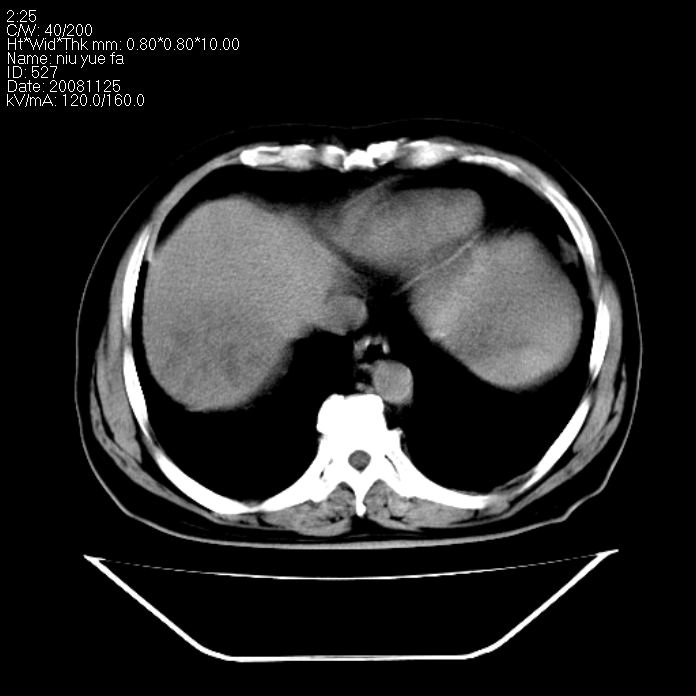

巨块型肝癌,坏死,出血;胆囊结石

1)考虑肝右叶巨块型肝癌并坏死、出血;建议行ct增强扫描检查进一步明确诊断。2)胆囊结石,胆囊炎。

考虑肝右叶巨块型肝癌并坏死、出血;建议行ct增强扫描。胆囊结石。

肝右叶巨块型肝癌并坏死、出血;胆囊结石,胆囊炎。